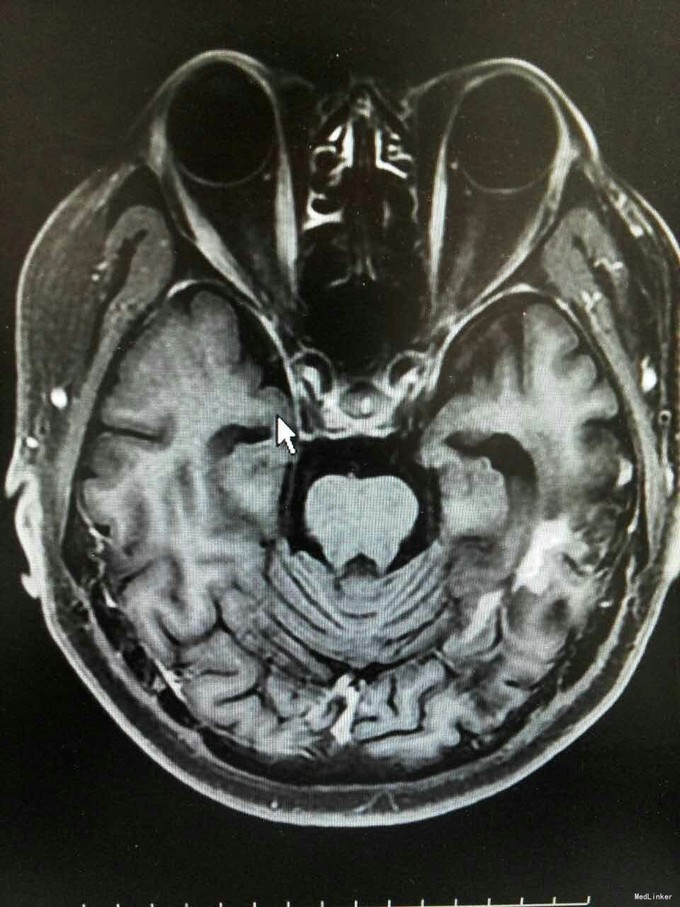

患者姜磊,男,49岁,主因"发作性视野缺损、失认8年余"于2015-11-20再次入我院,患者缘于8年前无诱因出现发作性视野缺损,伴阅读能力、理解力、认知能力下降,每次发作症状持续约3-5分钟左右,可自行缓解,无意识丧失、视物旋转、言语不利,无肢体活动障碍、大小便失禁。入院复查头颅MRI平扫+增强示:原左侧小脑幕、颞叶炎症治疗后,与2014-09-10日片比,病灶较前增多、增大。8年来间断在我院以:颅内非特异性炎症、症状性癫痫、高血压病 住院治疗,患者症状时轻时重,病灶反反复复,激素治疗有效。 病史汇报: 于2007年12月12日因"发作性视野缺损、失认1月"入我院,查头颅MRI示:左侧幕上颞底片状异常信号,并局部强化,考虑:炎症可能,肿瘤不排除;行腰穿检查,颅压120mmH2O ,外观清亮,脑脊液常规、生化均正常。脑电图轻度异常。给予复方磺胺甲恶唑片、青霉素、阿昔洛韦、激素(醋酸泼尼松片)等治疗。 2008年1月8日复查头颅MRI示:原左侧幕上颞底炎性病变范围缩小,综合考虑原颅内病变为炎性病变。于2008年1月19日出院,共住院37天。出院后仍间断出现发作性视野缺损症状。于2008-5-6复查头颅MRI示原左颞叶病变范围有缩小,支持局灶性脑炎的诊断。于2008.5.22~6.12予青霉素480万单位2/日巩固治疗30天。鉴于反复出现发作性视野缺损症状,于2008.6.5诊断性服用卡马西平片后上述症状未再发作,于是坚持服用卡马西平片(0.1g3/日)1年,服药期间未再出现发作性视野缺损症状。 于2012-05-29再次因"发作性双眼右侧视野缺失、闪烁感6天"入院,查头颅MRI示:原左侧幕上颞叶病变治疗后改变,考虑为炎性病变,结核可能。行腰穿示压力125mmH2O,脑脊液常规:颜色:无色,透明度:水样透明,潘氏试验:阴性,红细胞计数:80×106/L,白细胞计数:0x106/L,单个核细胞75%,多核细胞20%,脑脊液生化:蛋白508mg/L,葡萄糖3.3mmol/L,氯化物115.4mmol/L。脑电图印象:基本节律为低-中幅的α波, 频率调幅调节欠佳,分布可,左侧枕区波幅可见较右侧枕区减低。头前区可见少量低幅θ波及β波。深呼吸中见4-5hz慢波增多,有时呈短至中程节律,头前区为著,左侧偏胜。深呼吸后恢复好。睁闭眼试验:半抑制。闪光刺激:未见异常。脑电地形图:以α功率为主,可见θ功率。结论:轻度弥慢性异常脑电图及地形图;给予改善循环、营养神经、活血化瘀、脱水、激素等对症治疗。住院期间未再出现上述发作。 于2013-1-5再次因"发作性双眼右侧视野缺失、闪烁感1周。"入院,行头颅MRI示:左侧颞叶病变治疗后改变,与2012-07-24日片比,左侧小脑幕病变较前增大,左侧颞叶出现新病灶。给予改善循环、营养神经、活血化瘀、抗癫痫、抗感染(青霉素)、激素冲击(甲强龙)治疗后病情好转,于2013-4-15复查头颅MRI病灶再次缩小。患者出院后上述症状仍偶有发作。 于2014-5-12、2014-9-10复查头颅MRI病灶有增大趋势,再次给予抗炎(激素)等对症治疗后,于2014-11-24再次复查头颅MRI示:原左侧小脑幕、颞叶病变治疗后改变,与2014-09-10日片比较,较前明显缩小,水肿较前明显减轻。